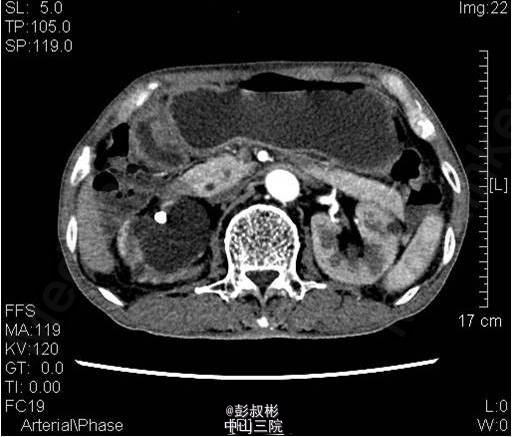

3、既往病史:既往“高血压”病史20年余,自服硝苯地平。“脑梗死”病史半年余,规律服用抗凝药物。 4、入院查体:无明显阳性体征。 实验室检查: 2015-01-11 肌酐101.2umol/L 。 2015-01-13总前列腺特异性抗原1.1ng/ml,游离前列腺特异性抗原0.3ng/ml。 2015-01-15 白细胞总数3.21x10E9/L,红细胞总数2.61x10E12/L,血红蛋白浓度78g/L,肌酐131umol/L ,白蛋白27g/L。 影像学检查: 2014-12-30心电图:完全性右束支传导阻滞。 2014-12-30全腹螺旋CT 检查所见:1、前列腺增生并钙化,建议MRI增强进一步检查除外合并肿瘤性病变。2、右侧盂管交界处结石并重度梗阻性肾积水,右肾结石;左肾多发钙化灶;左肾多发囊肿。3、慢性胆囊炎。4、双肺下叶多发小结节。 2015-01-14核素肾动态显像+GFR双血浆测定:右肾灌注、功能重度受损。左肾灌注正常,功能中度降低。肾小球滤过率:左肾为23.4ml/min,右肾为9.0ml/min。 2015-01-15彩超心脏:二尖瓣反流(轻度)。三尖瓣反流(轻度)。左室收缩功能正常。左室舒张功能减退。

5、目前诊断:1、右侧重度肾积水2、双侧肾结石3、左肾多发囊肿4、慢性胆囊炎